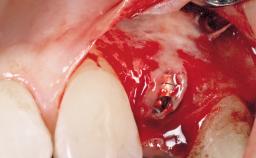

Immediate Flapless Placement of an Implant in a Maxillary Left Central Incisor Site

Placement Protocol Immediate implant placement

Socket Morphology Single-root socket

Socket Integrity Damage to one or more bone walls

Bone Volume Damage to one or more socket walls